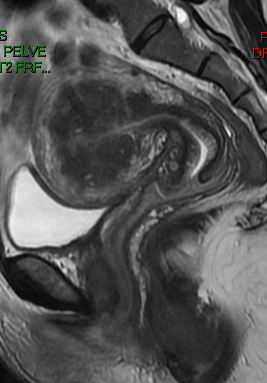

Paciente 38 anos, com quadro de dor pélvica e dismenorreia há cerca de três anos, com piora evolutiva. Foi solicitada ressonância magnética da pelve para melhor avaliação e investigação do quadro.

Diante dos achados de imagem, qual a sua principal hipótese diagnóstica?

AAdenomiose

BHiperplasia endometrial atípico

CCâncer de endométrio

DLeiomioma uterino